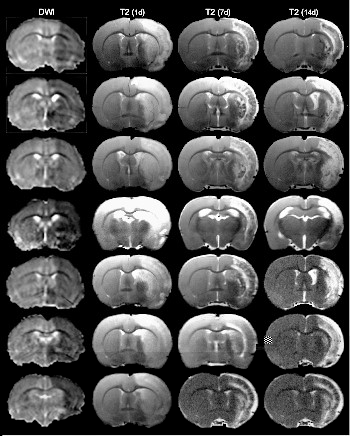

Study and development of new therapeutic strategies in neuronal pathologies, mainly related to cerebral ischemia. Our perspective is to try that all the knowledge developed in the field of research has a translational application and that it has an impact on the benefit of the patient.

1. Neuroprotection against excitotoxic damage in cerebral ischemia and ALS.